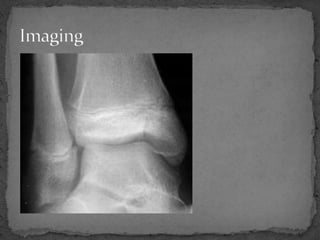

An 11-year-old male presented to the emergency department after being kicked by a cow, unable to bear weight on his right leg and experiencing excruciating pain. Examination revealed swelling and bruising around the right ankle with pain on movement. X-rays showed a fracture extending from the metaphysis through the epiphysis, classified as a Salter-Harris Type IV injury. This type of injury crosses the physis and involves both the epiphysis and metaphysis, is associated with a worse prognosis than other types, and may affect growth even with perfect reduction. Orthopedic consultation was recommended for possible open reduction and internal fixation if any displacement was present.